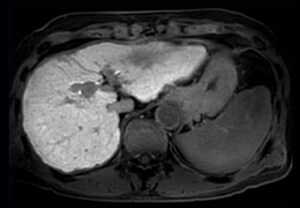

Cine 2D BFFE (4 CAV)

Elition X 3.0T

Hospital Metropolitano de la Policía de Tokio, Japón